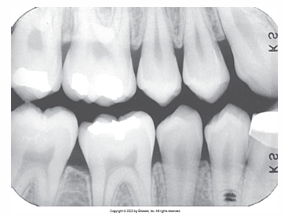

What is the problem with this OVERDEVELOPED FILM X-ray?

Appears dark, Excessive developing time, Developer solution too hot, Inaccurate timer or thermometer, Concentrated developer solution

How would you resolve this OVERDEVELOPED FILM X-ray?

Check development time • Check developer temperature • Replace faulty timer or thermometer • Replenish developer with fresh solutions as needed